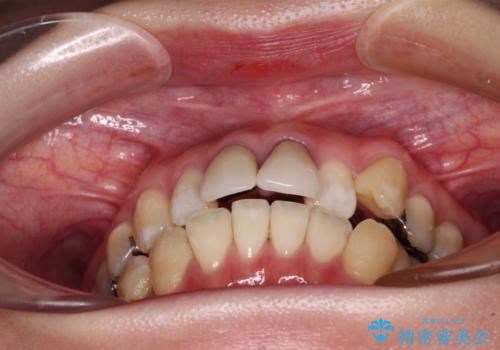

- 前歯のデコボコとセラミッククラウン周りの黒い縁を気にして来院された患者様です。

前歯の黒い縁は、矯正治療後にオールセラミッククラウンにて改善することとしましたが、いち早く目立たなくしたいとのことで、事前に矯正治療用仮歯に置き換えてから矯正治療を開始しました。